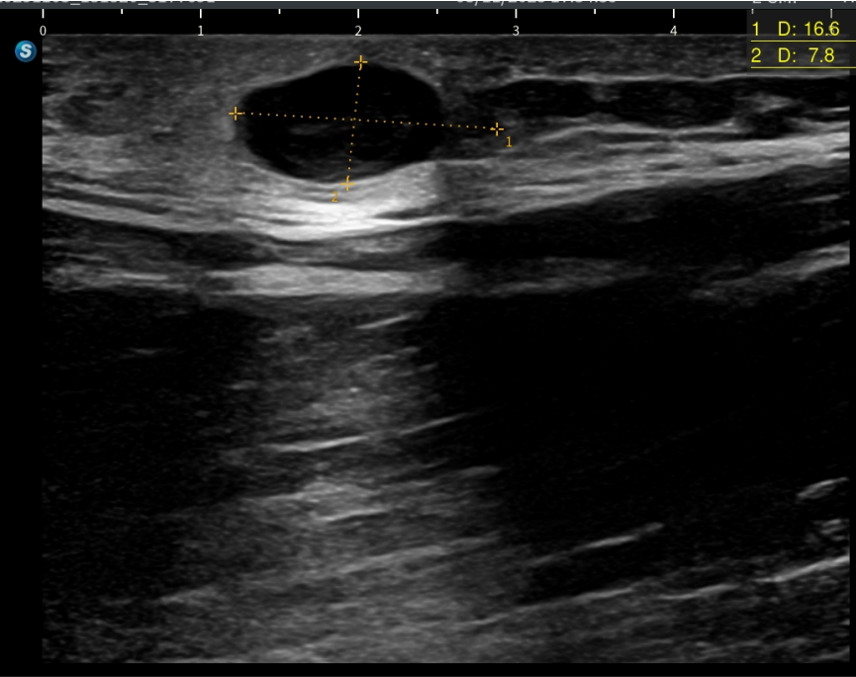

Hallazgos ecográficos

Lesión hipoecogénica de unos 13 x 9 mm, bien delimitada con refuerzo acústico y artefacto de borde compatible con quiste epidérmico.

Se planifica cirugía menor en Atención Primaria y se extirpa una vez localizado el pedículo vascular para evitar sangrado. Se envía material extirpado a anatomía patológica con resultado de quiste epidérmico.